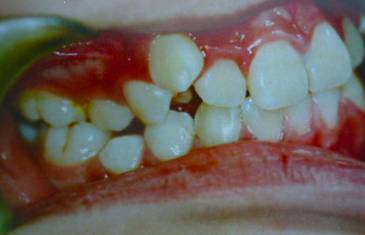

牙齿需要矫治的患者,往往牙齿和排列和咬合关系多会出现错乱,那些错乱的牙齿即使不拔除,它也是没有功能的,因为它和对颌的牙齿咬不上。

并且,这些排列不正常的牙齿很难清理干净,容易在它的周围存留很多食物残留,久而久之就形成蛀牙,最后也是一拔了之。我们医生拔牙的时候有一定选择的,一般是拔除那些坏牙、没有功能的牙。

拔牙的目的是为了给前突、拥挤的牙齿提供足够的间隙,另外还用于调整牙齿的咬合关系。所以问题是:你牙齿间的这些可以用的空隙有多少?如果多,那就好办,不拔牙可以;如果少,那还是有可能要拔牙。